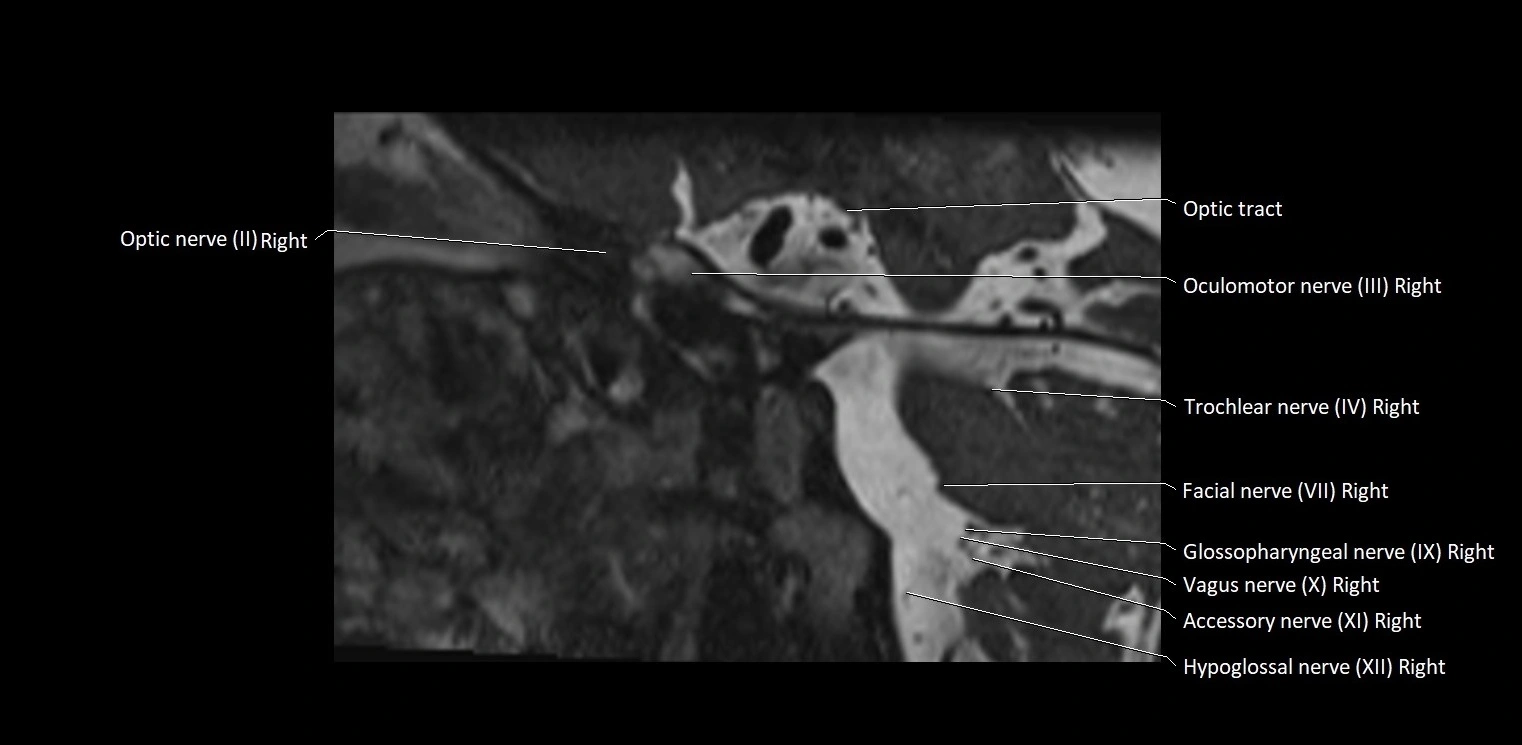

MRI Appearance

• The abducens nerve is a small, thin, linear structure

• Best visualized on high-resolution T2-weighted 3D MRI sequences (e.g., FIESTA or CISS)

• Seen as a hypointense (dark) line running from the brainstem at the pontomedullary junction, traversing the prepontine cistern, and entering Dorello’s canal under the petrosphenoidal ligament, then into the cavernous sinus, and finally the orbit

• May be challenging to visualize in standard MRI due to its small size

• Pathology may be inferred by absence, displacement, or enhancement of the nerve

MRI images

image